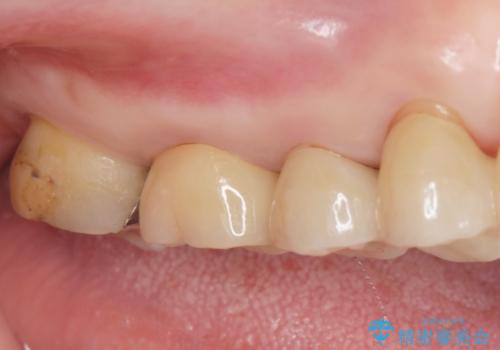

拡大鏡下で虫歯を取り切った後、フルジルコニアクラウンにて治療しました。

適合の良い被せ物が入りました。